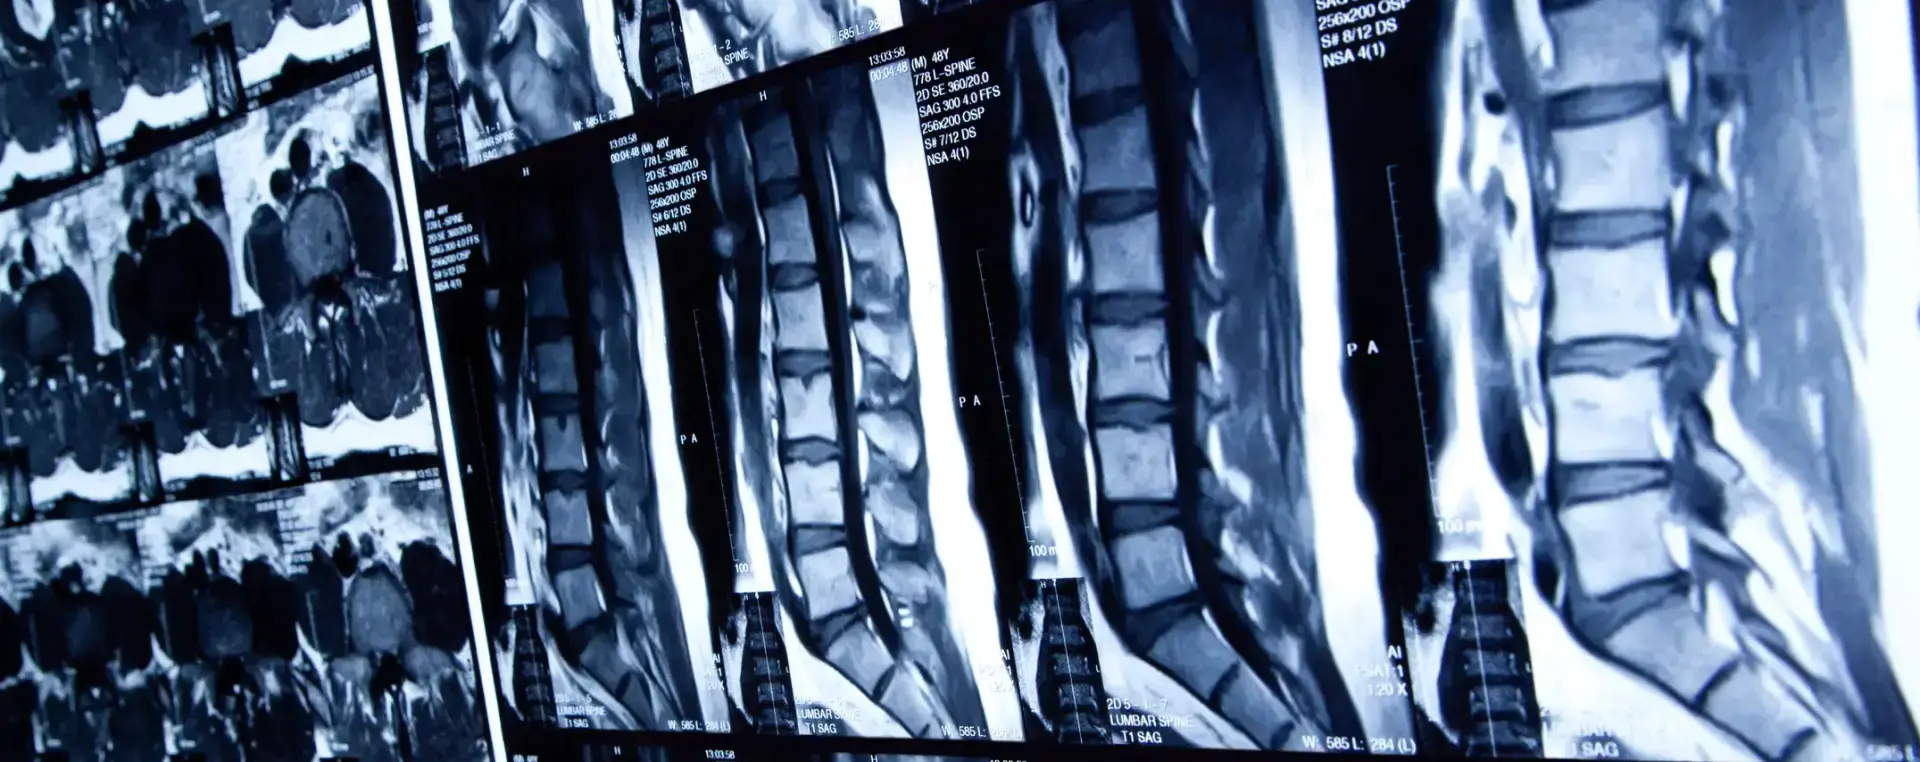

Spinal cord injuries can be caused by damage to any part of a person’s spinal cord or the nerves at the end of the spinal canal. These injuries are catastrophic and can easily cause permanent changes in strength, tactile sensation, and other crucial bodily functions. However, the severity of a spinal cord injury is based on how many nerve connections are severed in an accident and as such they are classified as either complete or incomplete.

Complete spinal cord injury occurs when there is a complete severance of nerve connections from the spine to the brain and all feeling and ability to control movement is lost. Meanwhile, an incomplete spinal cord injury occurs when there is a partial severance of nerve connections and as a result, there is partial motor or sensory function. Depending on the location and the nature of the accident, incomplete injuries are recoverable, but requires extensive physical therapy and possibly surgery.